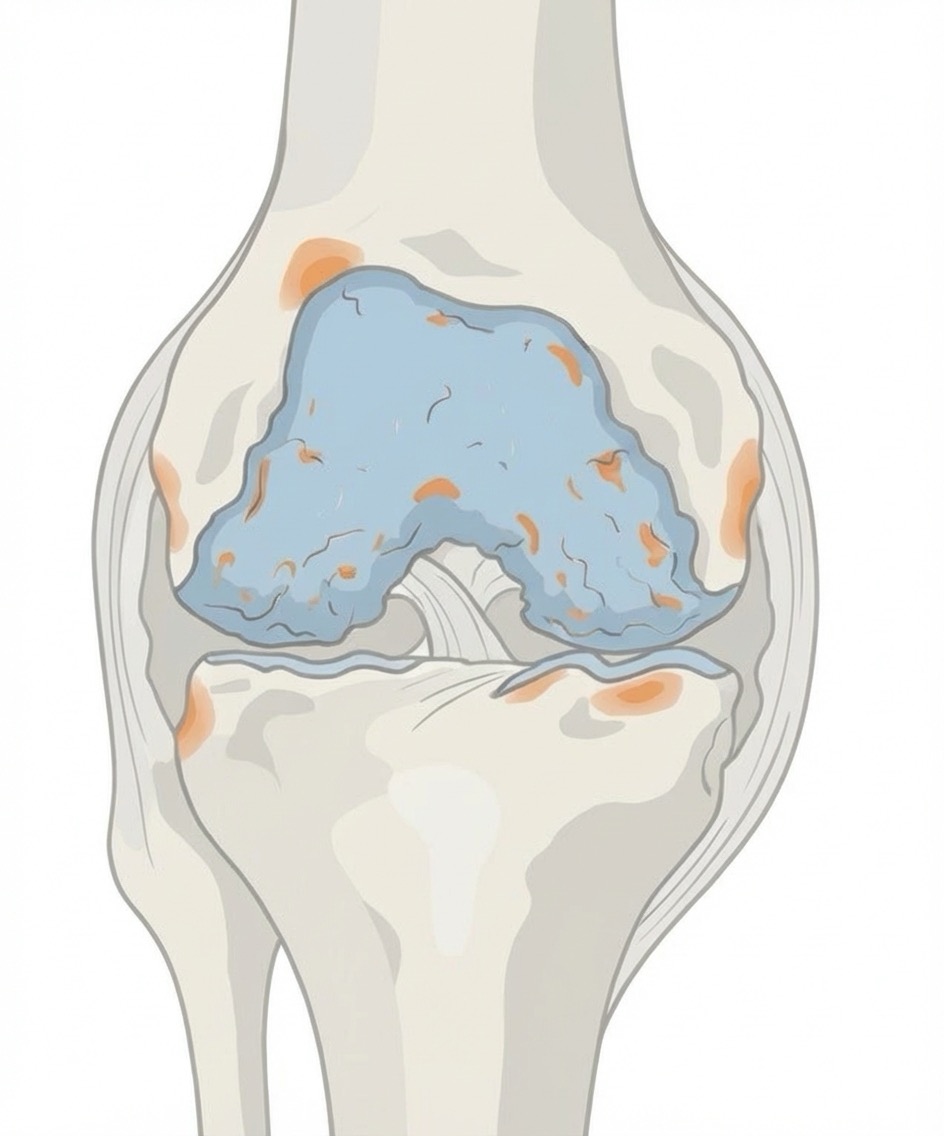

- Fortgeschrittene Kniearthrose (Gonarthrose)

- Rheumatoide Arthritis des Kniegelenks

- Schwere Verletzungen (posttraumatische Arthrose)

- Knochennekrose (Osteonekrose)

Eine Knie-TEP wird empfohlen, wenn konservative Behandlungen (Medikamente, Physiotherapie, Injektionen, Orthesen) nicht mehr ausreichend helfen und Sie unter anhaltenden Schmerzen sowie deutlichen Bewegungseinschränkungen im Alltag leiden. Typische Indikationen sind fortgeschrittene Arthrose (Gonarthrose), rheumatoide Arthritis, posttraumatische Arthrose oder Knochennekrose.

- Teilprothese (Schlittenprothese/unikondyläre Prothese): Ersetzt nur den geschädigten Teil des Kniegelenks (medial oder lateral). Geeignet bei isoliertem Kompartmentschaden mit intakten Bändern.

- Vollprothese (Totalendoprothese): Ersetzt alle drei Gelenkkompartimente. Notwendig bei fortgeschrittener Arthrose in mehreren Bereichen.